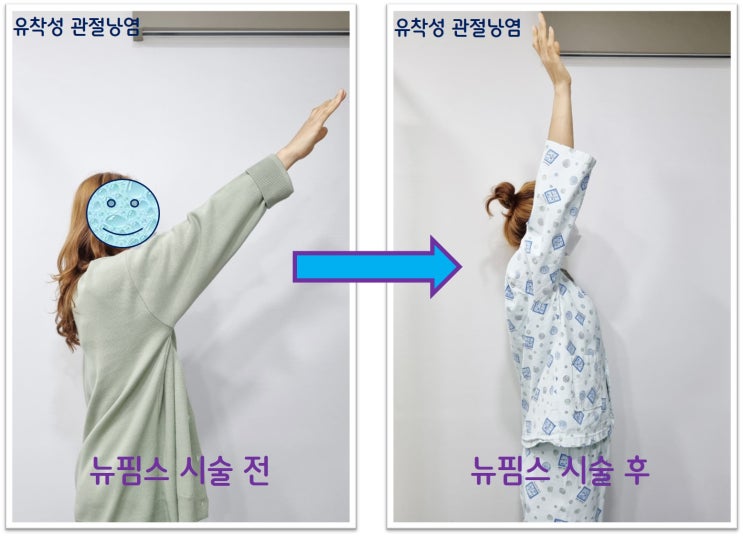

시술 다음날 가동범위를 다시 검사한 사진을 보면